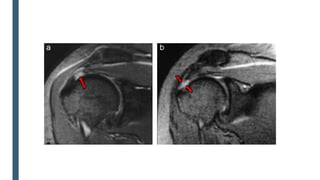

■ Resonancia magnética

Retracciòn excesiva de los tendones y atrofia muscular son indicadores de pobre resultado quirúrgico.

Sensbilidad 80-97%

CONFIRMAR LA IMPRESIÓN DIAGNÓSTICA CLÍNICA